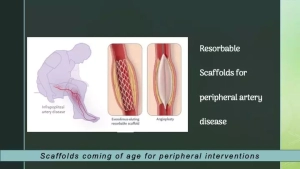

Resorbable scaffolds fare better than balloon angioplasty for infra-popliteal artery disease :NEJM

In patients experiencing chronic limb-threatening ischemia (CLTI)…